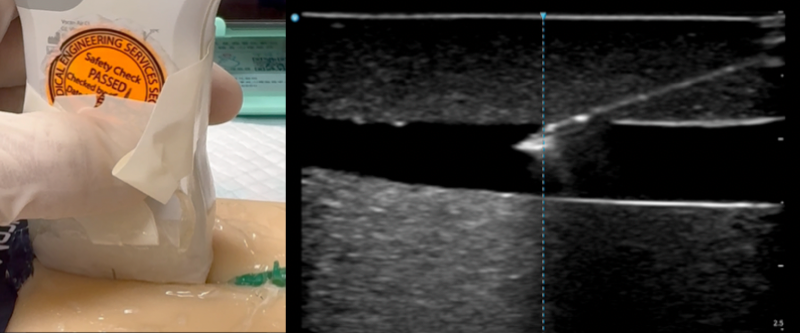

🚅Long Axis Approach

The long axis approach is also called the in-plane or longitudinal approach. As the name implies, the structures are all in-plane with the ultrasound beam. This approach is technically more demanding since one had to cut both the vessel and the fine needle along their long axis with one plane of narrow ultrasound beam. Contrary to the short axis approach, only the needle moves while the probe should remain stationary throughout the insertion. Therefore, the initial placement of the probe to obtain an optimal long axis view is crucial. This approach require precise movements and excellent hand-eye coordination. You should begin with short axis approach first. Advance to practising long axis approach only when you are comfortable with short axis.

- Insert the needle and advance slowly

- Tent and pop the vessel wall